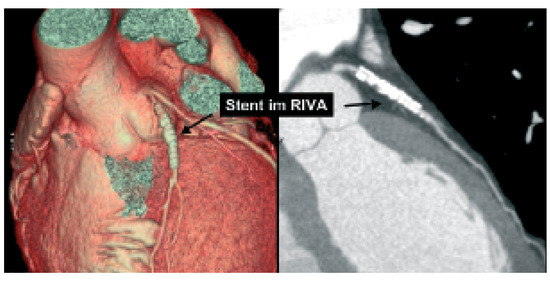

Biventricular pacing is an accepted therapy in patients suffering from terminal heart failure. Main obstacle however is the positioning of the left ventricular electrode via coronary sinus as well as its reliable fixation. This article describes in a...